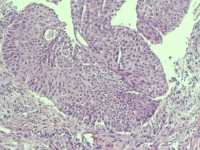

性别

女

年龄

38岁

临床诊断

宫颈病变

一般病史

宫颈癌筛查:HPV52(+)

标本名称

宫颈6点组织

大体所见

灰白色组织1块

可以诊断CIN几级

图2

HSIL(CIN3)累腺